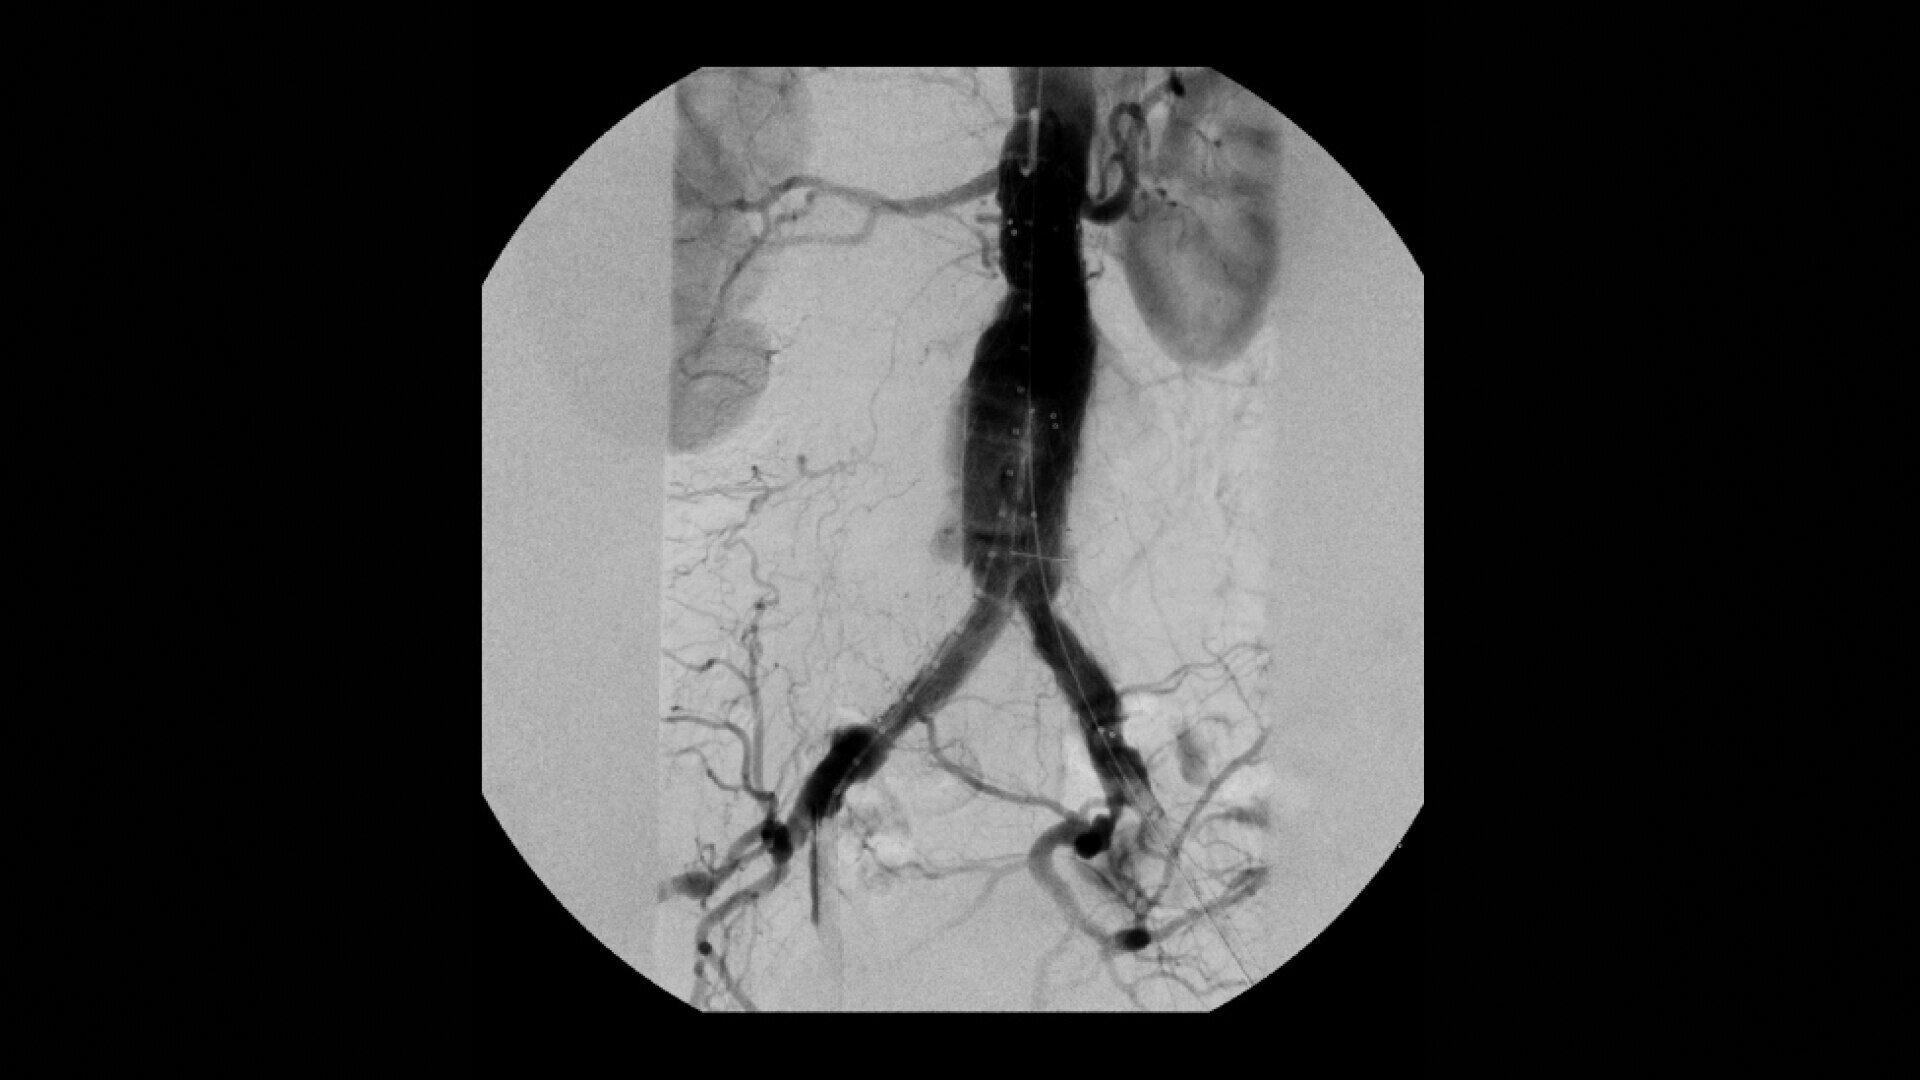

OEC C-arms are used by interventionalists and surgeons to obtain vascular imaging during peripheral to contrast run-off procedures. Superb resolution, even in the presence of motion, enables easy identification of anatomical landmarks and the extremity of the catheter, even as catheter tip moves.

Clearly see 0.014” guidewires in chest and abdomen region or 0.008” guidewires in peripheral vascular with the OEC Elite CFD with a flat detector, image processing advancements and 4K viewing display.

Experience fixed room-like images with eNR (enhanced Noise Reduction), an advanced software algorithm that automatically reduces image noise by 30% for an equivalent appearance of 30 kW power.

•Abdominal aortic aneurysm (AAA) stent and balloon deployment

• Infrarenal aortic aneurysm repair

• Recanalization and stent placement in iliac arteries